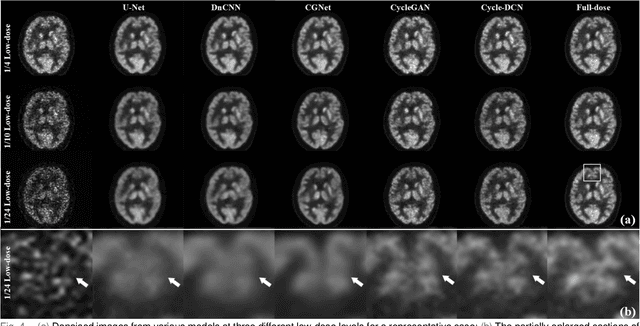

Abstract:Positron emission tomography (PET) is a critical tool for diagnosing tumors and neurological disorders but poses radiation risks to patients, particularly to sensitive populations. While reducing injected radiation dose mitigates this risk, it often compromises image quality. To reconstruct full-dose-quality images from low-dose scans, we propose a Cycle-constrained Adversarial Denoising Convolutional Network (Cycle-DCN). This model integrates a noise predictor, two discriminators, and a consistency network, and is optimized using a combination of supervised loss, adversarial loss, cycle consistency loss, identity loss, and neighboring Structural Similarity Index (SSIM) loss. Experiments were conducted on a large dataset consisting of raw PET brain data from 1,224 patients, acquired using a Siemens Biograph Vision PET/CT scanner. Each patient underwent a 120-seconds brain scan. To simulate low-dose PET conditions, images were reconstructed from shortened scan durations of 30, 12, and 5 seconds, corresponding to 1/4, 1/10, and 1/24 of the full-dose acquisition, respectively, using a custom-developed GPU-based image reconstruction software. The results show that Cycle-DCN significantly improves average Peak Signal-to-Noise Ratio (PSNR), SSIM, and Normalized Root Mean Square Error (NRMSE) across three dose levels, with improvements of up to 56%, 35%, and 71%, respectively. Additionally, it achieves contrast-to-noise ratio (CNR) and Edge Preservation Index (EPI) values that closely align with full-dose images, effectively preserving image details, tumor shape, and contrast, while resolving issues with blurred edges. The results of reader studies indicated that the images restored by Cycle-DCN consistently received the highest ratings from nuclear medicine physicians, highlighting their strong clinical relevance.